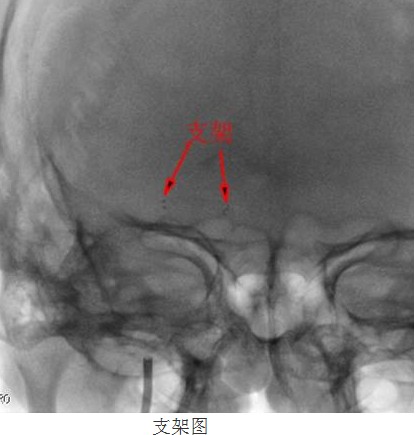

常规准备后,神经内科颜津津主治医师在助手高彬医师配合下采用Seldinger法穿刺股动脉,置导管鞘、引导管,在导丝带引下将导引导管放置右侧颈内动脉岩部造影,后在透视下,顺着造影路图,小心将微导丝、微导管通过狭窄处并置入右侧大脑中动脉M3段,接着撤出微导管,顺着微导丝置入Gateway球囊, 至狭窄部位,经造影骨性标志等多重定位后证实球囊位置良好,接压力泵缓慢加压扩张,撤出球囊造影,显示血管成形良好。选取Wingspan支架, 顺微导丝将支架输送器小心送至狭窄处,造影定位确认支架位置准确覆盖狭窄部位,释放支架,撤出支架输送器,造影证实血管狭窄处成形良好,观察10分钟后再次造影,支架无移位,狭窄处远端血管完整,未见血管狭窄、造影剂外渗。撤除导丝、导引导管,患者术后24小时可下床自行活动,术后1周顺利出院,生活基本恢复正常,并叮嘱梁伯继续坚持服药,定期复诊。